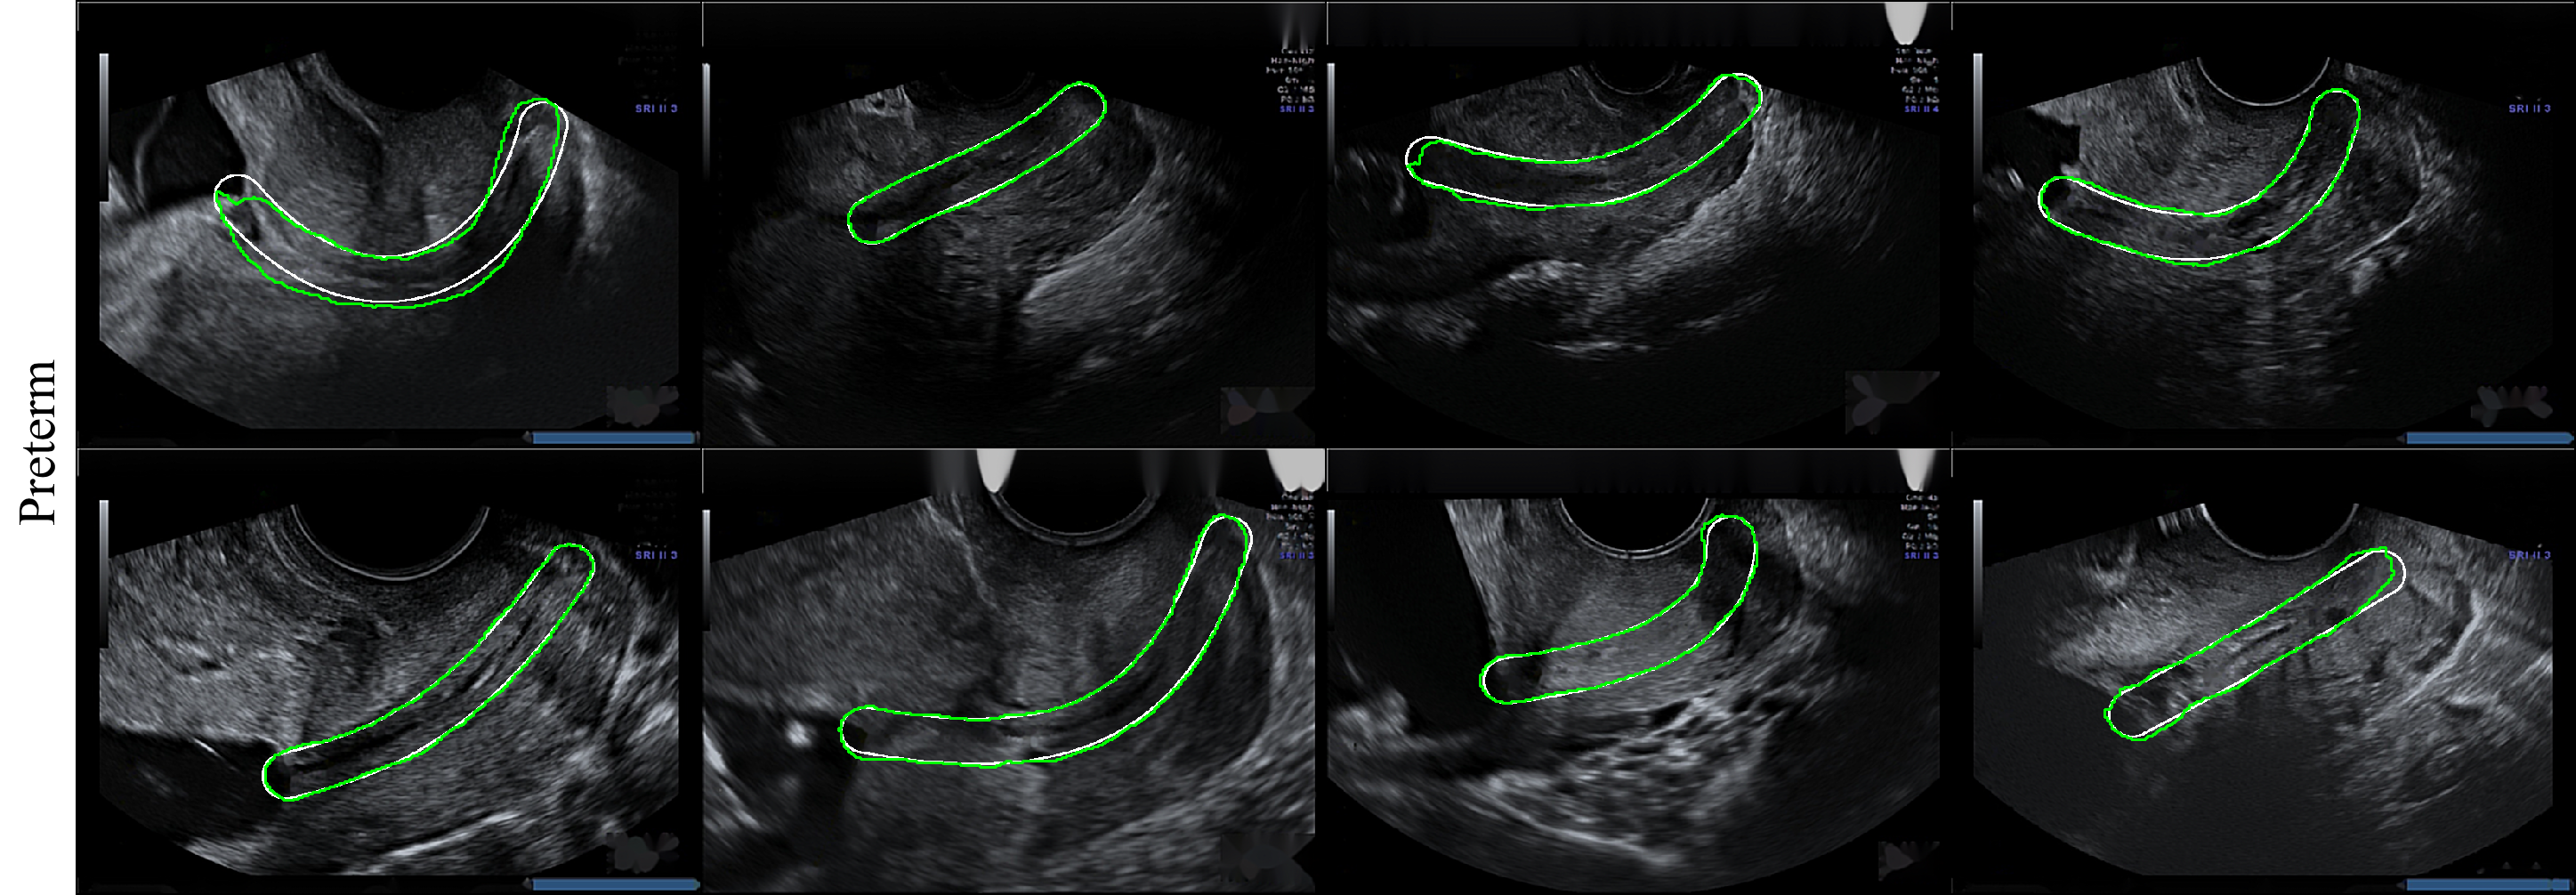

We achieved good segmentation results due to the easy structure of the cervix, which is relatively large in the ultrasound image. In Fig. 4 we show examples of retrieved cervix segmentation masks for each of the classes. From these examples, it can be seen that our proposed method was able to localise cervixes which are subject to variability in scale and appearance. Table 2 shows the quantitative performance of the proposed method in terms of mean std of IoU coefficient, precision, recall and AUC.

We validated three models against the cervix segmentation task applied to transvaginal ultrasounds images: FCN, DeepLab and U-Net. Visualization of results for segmentation are presented on Fig. 3. As shown in Table 1, the best performing results were achieved by U-Net. U-Net is built upon the architecture of FCN. Besides the increased network depth to 19 layers, U-Net benefits from a superior design of skip connections between different stages of the network. The most important advancement of U-Net over FCN is the shortcut connections between layers of equal resolution in the analysis path to expansion path. This gives U-Net better performance because it has multiple upsampling layers along with more skip connections which make it more robust to scale variations as compared to FCN.

We chose the U-Net based network for the classification task for several reasons. First, we obtained the best segmentation result qualitatively. The U-Net network best predicts edges that help us classify images based on the shape of the cervix. In addition, the U-net network contains the least parameters among the other networks tested, without requiring a large number of images and length of training to get a good performance.